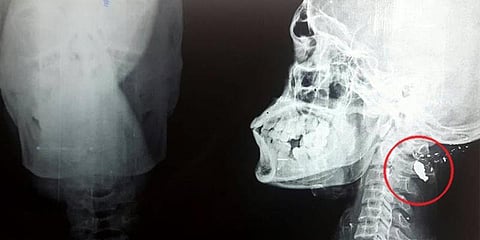

வீட்டுக்கு வந்ததும் சுராஜுக்கு கடும் தலை வலி. தூங்க முடியவில்லை. காலையில் அந்த டாக்டர் சொன்னவாறு அதே மருத்துவமனைக்குச் சென்றனர். எக்ஸ்ரே எடுத்து பார்த்த டாக்டர்கள், பின்பக்க மண்டையில் ஏதோ இருப்பதாக நினைத்தனர். ஆனால், அது என்னவென்பது அவர்களுக்குத் தெரியவில்லை. நான்கைந்து டாக்டர்கள் கூடி பேசியும் அவர்களுக்கு இது என்னவென்பது தெரியவில்லை.

இதையடுத்து அவர்களை வேறு மருத்துவமனைக்கு டாக்டர்கள் அனுப்பி வைத்தனர். அங்கு பரிசோதித்த டாக்டர்கள், அது புல்லட் என்பதை உறுதிப்படுத்தினர். பின்னர் நான்கு மணி நேரம் ஆபரேஷன் செய்து அதை நீக்கினர். சுராஜை சுட்டது யார்? அல்லது நள்ளிரவில் அவர் மண்டைக்கு கீழே குண்டு பாய்ந்தது எப்படி? என போலீசார் விசாரித்து வருகின்றனர்.